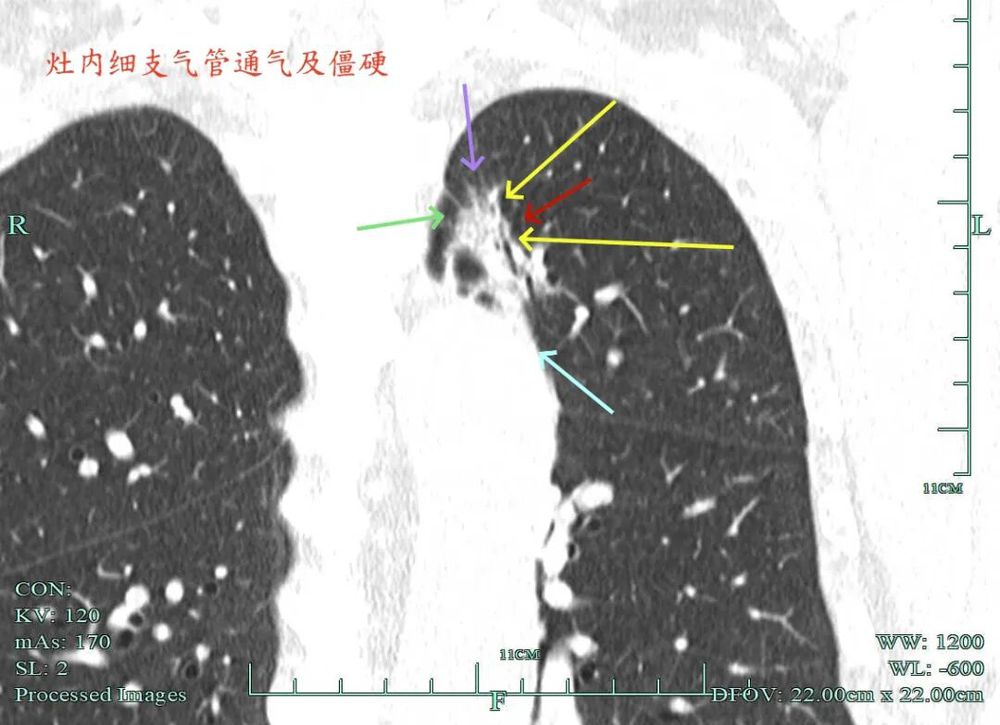

杭州市肿瘤医院影像展示与分析:

右上也有混合密度结节,实性部分缺乏膨胀性与收缩力,磨玻璃成分较淡,也偏糊,但持续存在仍得考虑肿瘤范畴可能性大。

此视角是混合密度,实性为主,贴胸膜近。

左侧主病灶长达三年半时间的随访,当时就是混合密度,整体轮廓较清,随访不好转的话就是要高度警惕恶性的。现在病灶已经明显进展,实性成分增多明显,考虑浸润性腺癌可能性大。肺的粘膜相关B细胞淋巴瘤一般缺乏毛刺征,整体病灶的轮廓与边界会再偏模糊点。但从三年多随访范围增大不多,仍有磨玻璃成分来讲,个人认为已经有转移了的概率可能并高。大概率是中分化浸润性癌可能性大些。右侧病灶也是要考虑浸润性腺癌的,但一是它小些,二是处理要先处理风险更大的一侧,所以右侧病灶拟后续随访叶视其进展再微创干预。

今天这位结友的病理类型稍差于术前的预测,但从其三年多随访情况来看,进展不算大厉害,第10组与第12组淋巴结均阴性的话,还是真早期的可能性还是较大的。后续倾向暂随访观察,可以采取相对稍积极的随访策略,比如两年内4个月复查一次,三到五年内半年复查一次,五年后再年度复查;而且右侧的病灶要在随访进展或身体恢复良好后微创局部楔形切除。期间万一有转移,其实是伪早期的话,则基因检测并全身性治疗。其实今天这种病灶在临床中被判断为炎性的并不少见,尤其是非胸外科医生。因为胸外科的一般相对积极,警惕性高些。在我的公众号上其实也分享过多例这种看着似乎是炎性,但长时间随访不好转,或缓慢进展的病灶其实是浸润性腺癌的一种特殊表现,不少见的。我感觉此类病灶比较主要的临床特征是:1、密度多是混合磨玻璃密度,实性成分较明显,磨玻璃成分较淡,病灶显得密度较为杂乱不均;2、整体形态膨胀性不明显,收缩力不太强;3、灶内支气管通气及显得较为僵硬,血管征不典型,但表面多是不平不规则,较为毛糙,分叶多可见;4、随访或抗炎治疗不好转,进展不快,相对较为缓慢。容易被人以为是慢性炎症。但此时我们要注意几点:1、寻找磨玻璃成分,并观察瘤肺边界,尤其是磨玻璃成分与周围正常肺组织之间的界限是否清楚,清楚的多是恶性;2、靶重建从不同角度观察病灶形态,看病灶与邻近结构的关系,有无推压、破坏或支气管截断等征象;3观察病灶内部通气支气管的形态,扭曲、僵硬不舒展的多容易是恶性病变。总体上,要对“影像看着像慢性炎,但随访持续存在且有磨玻璃成分的”病灶要特别提高警惕,对于靠近边缘部分的,手术创伤不大的,要考虑“开刀带来创伤与随访导致的风险”之间的利弊权衡。我的根本理念仍是:淡化最后病理结果,从风险角度考虑问题!